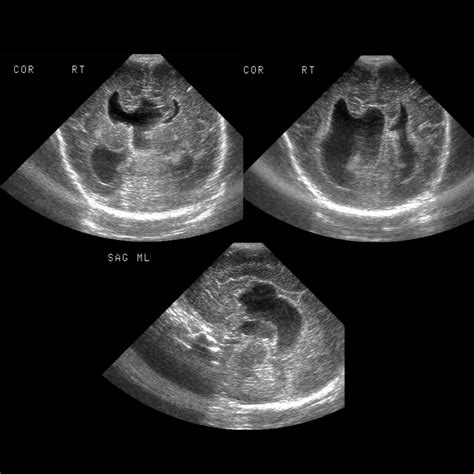

Fetal Ultrasound Prenatal screening Moderate, can miss subtle cases.

Diagnosis typically occurs through medical imaging, often initiated by a pediatrician or neurologist when developmental delays are noted. Because the condition is structural, standard imaging is the primary diagnostic tool used by clinicians.